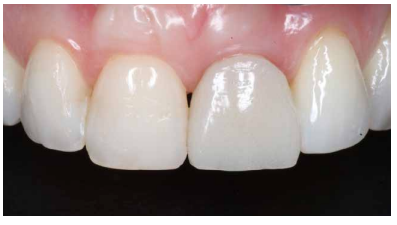

Los beneficios de la carga inmediata incluyen una reducción notable de las intervenciones quirúrgicas, una menor dilatación temporal del tratamiento e incluso un mejor bienestar psicológico y social para el paciente. En casos con importante compromiso estético, la carga inmediata o la provisionalización inmediata, añadida a la colocación inmediata postextracción del IOI permiten minimizar las alteraciones derivadas de la pérdida dental, manteniendo el perfil de emergencia, contorno de tejidos blandos y las papilas gingivales5-7.

Así mismo, se han establecido diferentes protocolos para el manejo del sector estético anterosuperior, que se suman al acto de la colocación inmediata del implante y la corona provisional, donde se incluyen la colocación de un material no reabsorbible entre el IOI y la cortical vestibular para minimizar el posible colapso, así como el manejo de los tejidos blandos periimplantarios8-11.

Conclusiones: La rehabilitación sobre implantes en situaciones de pérdida dental en el sector anterior estético y en especial, en pacientes jóvenes, requiere un plan de tratamiento multidisciplinar en cuanto a la extracción del diente y colocación del IOI en la posición tridimensional correcta, existiendo diferentes aspectos a tener en cuenta para ello, especialmente el remanente óseo residual, la posición del margen gingival, así como la preservación y acondicionamiento de los tejidos duros y blandos periimplantarios mediante injertos y un manejo correcto de una prótesis provisional hasta conseguir un perfil de emergencia y contorno gingival ideal antes de la corona definitiva

Conclusions: Rehabilitation on implants in situations of tooth loss in the aesthetic anterior sector, especially in young patients, requires a multidisciplinary treatment plan in relation to tooth extraction and placement of the OII in the correct three-dimensional position. There are various aspects to be taken into account, particularly the residual remaining bone, the position of the gingival margin, as well as the preservation and conditioning of the peri-implant hard and soft tissues by means of grafts and proper handling of a provisional prosthesis until an ideal emergence profile and gingival contour is achieved before the final crown.